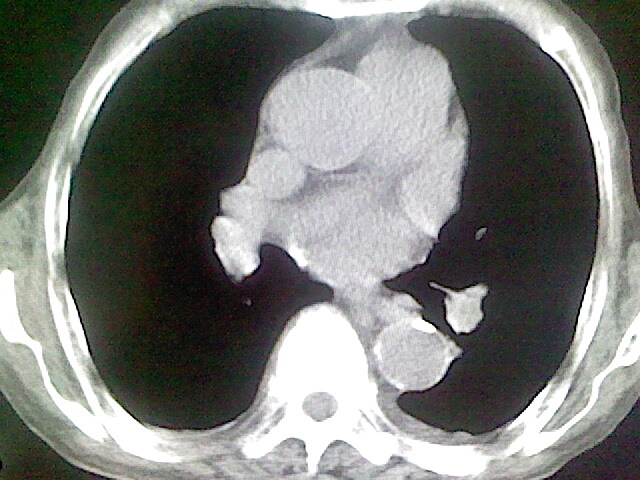

以下是引用zsl6918在2008-8-28 16:49:00的发言:[br]双肺炎性病灶,食管狭窄估计与心房增大压迫所致。

以下是引用xulianj在2008-8-28 20:36:00的发言:[br]慢支肺气肿伴感染,右上肺陈旧性结核;食道建议胃镜检查。

以下是引用wqs571018在2008-8-28 21:18:00的发言:[br]慢支继发感染,右上肺陈旧性结核;食道建议胃镜检查。